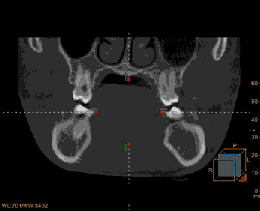

麦芽通过德国KAVO全景与3D口扫,一次性采集口内三维影像数据有效传递信息,使诊断分析及治疗预测实现可视化,完成矫治系统的个性化制作,全数字化设备避免数据采集误差与信息传输失真,致力更严谨、精确、精密的矫牙疗效!

• 德国KAVO全景

高精度重建三维图像具有指导意义

单颌100万个扫描点,对牙齿移动的控制达0.1°